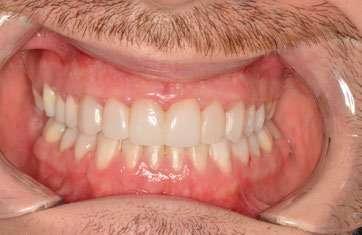

Tras 18 meses de tratamiento, se concluyó la fase ortodóncica y se colocaron las carillas de composite definitivas de canino a canino en la arcada maxilar, obteniendo los siguientes resultados:

1. Expansión maxilar efectiva junto con mejoría en la estética de la sonrisa (Ilustración 10):

 Se corrigió la mordida cruzada posterior bilateral disminuyendo los corredores bucales.

 La expansión obtenida fue > 5 mm, evidenciada en la tomografía post-tratamiento.

2. Corrección de la mordida abierta anterior (Ilustración 11):

 Extrusión controlada de los incisivos con alineadores y attachments.

 Reducción de la mordida abierta de 3 mm, logrando una sobremordida adecuada.

3. Mejora de la relación oclusal:

 Conversión de la relación molar y canina de Clase III a Clase I funcional.

 Centrado de las líneas medias.

Ilustración 10. Registros extraorales e intraorales finales.